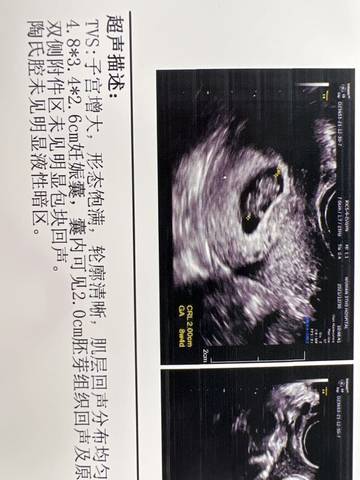

八周五天的B超,看看是男宝还是女宝呀?哈哈哈

journal_insert_pic_1688823005journal_insert_pic_1688823084journal_insert_pic_1688823112journal_insert_pic_1688823173